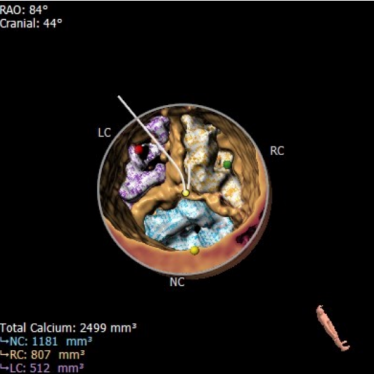

CT数据显示该患者为三叶三窦式主动脉瓣。

主动脉瓣瓣环周长77.0mm,平均周长径 24.5mm;LVOT周长89.1mm,平均周长径28.4mm;SOV:28.5mm*29.3mm*32.0mm;STJ平面周长94.6mm;瓣叶增厚,瓣上钙化明显,HU850积分1341mm³, HU560积分2499mm³,升主动脉最大直径44.1mm。

左冠开口高度11.0mm,右冠开口高度15.0mm,左冠高度较低,根据瓦氏窦内径和瓣叶长度综合判断,左冠堵塞风险不高;右冠瓣叶长度较长,存在一定封堵风险,合并患者原有冠脉疾病,考虑右冠灌注不良风险较高;左室腔增大,心室壁未见明显增厚。